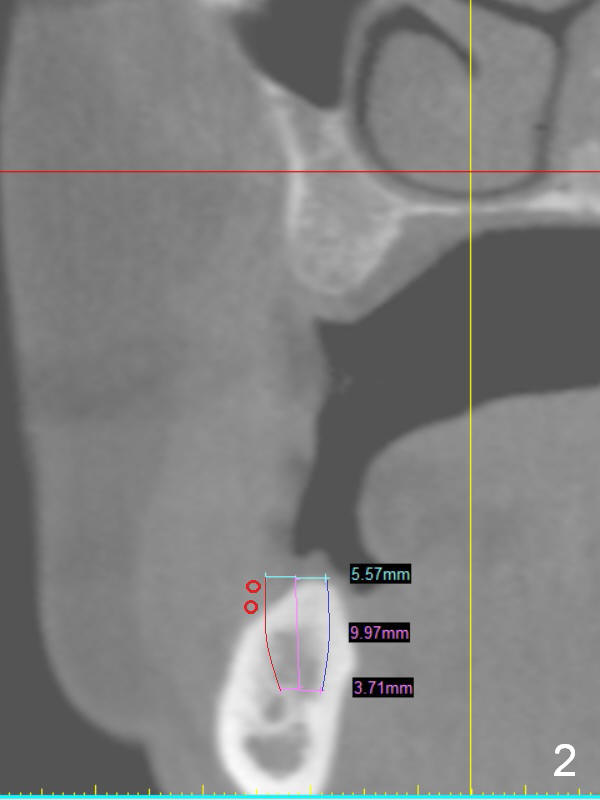

A 49-year-old lady is petit. An implant is placed at #3 and ready for restoration. The crest at #30 is narrow (Fig.1 ^). Bone density at the cortex, around the Inferior Alveolar Canal (IAC) and the medulla is D1, D2 and D3, respectively. It appears that a 10 mm bone-level implant is too close to IAC (Fig.2), whereas a 8 mm one has enough clearance (Fig.3,4). With the same diameter, there will be less thread exposure if the implant is placed a little lingually (Fig.4 (between arrows), as compared to Fig.3).

Since the patient is small and the cortex is dense, a 4.5x8.5 mm UF implant should meet masticatory force as long as #14 and 19 also receive implants. Her mouth should be small. Consider using sensor 1.舌侧骨板厚,适当磨去,让植体舌侧移动。